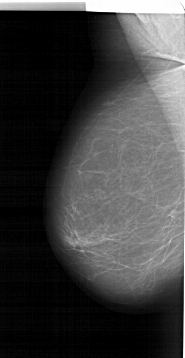

A_1986_1.LEFT_MLO

LEFT_MLO LINES 6076 PIXELS_PER_LINE 3136 BITS_PER_PIXEL 12 RESOLUTION 43.5 NON_OVERLAY